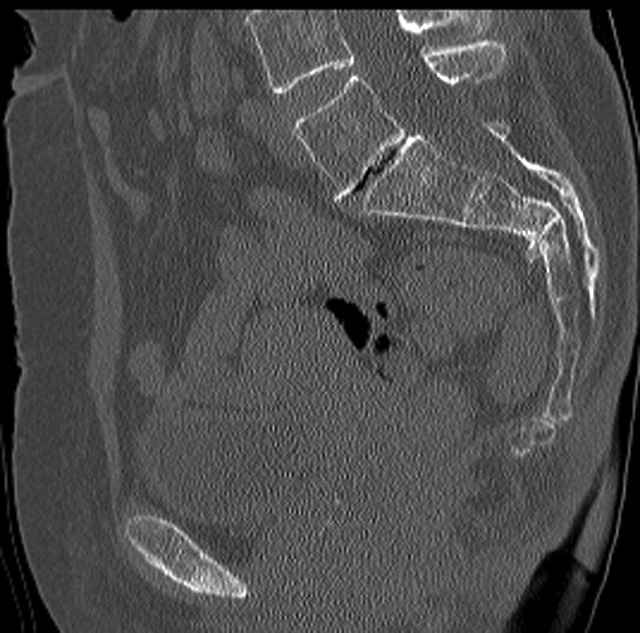

Pelvic CT Scan - 3 Months After Fall

Sacral Injuries

Ramus Fractures

Percutaneous Fixation